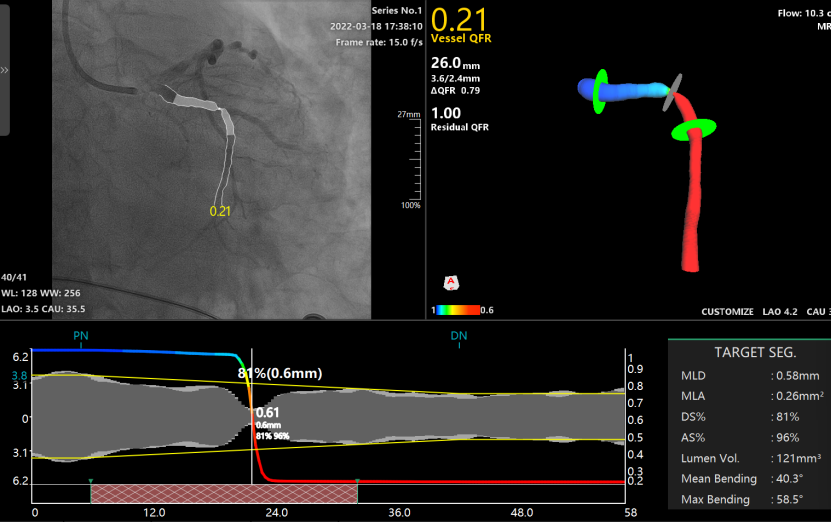

为了明确每一条血管腔的血流功能及精准指导血管支架的植入,避免植入不必要的支架,手术医生对三条血管进行了 QFR 检查,发现前降支、回旋支、右冠状动脉的 QFR 值分别为 0.89,0.21 和 0.37。根据 QFR 结果,手术医生需优先在回旋支植入支架,而对右侧血管择期治疗。

左回旋支的 QFR 测定及术中支架植入策略规划

结合 QFR 的虚拟支架技术和残余 QFR 值(Residual QFR),手术医生可以在支架植入过程中明确所需支架的大小型号及长度,并对植入后的血流恢复效果做出预判。

最后医生顺利为该患者植入了支架,重复冠脉造影显示支架贴壁良好,术后的回旋支 QFR 值恢复至 0.97,血流恢复明显且患者症状缓解。